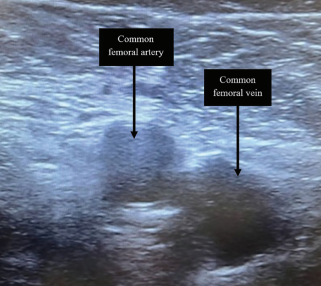

Osama T Niazi, DO, and Hend Bcharah, BS, provide an in-depth look at updates to their same-day discharge protocol, outlining eligibility criteria to identify suitable candidates, detailing advanced vascular access, and more.